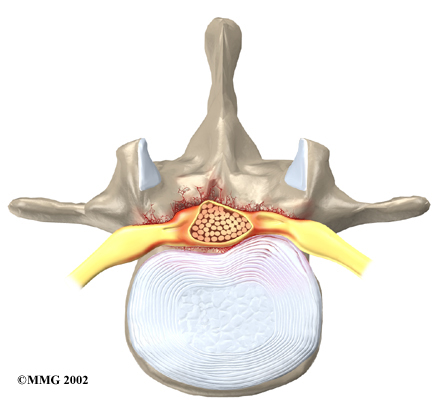

In the lumbar spine, the spinal canal usually has more than enough room for the spinal nerves. The canal is normally 17 to 18 millimeters around, slightly smaller than a penny. Spinal stenosis develops when the canal shrinks to 12 millimeters or less. When the size drops below 10 millimeters, severe symptoms of lumbar spinal stenosis occur.

Degeneration: Degeneration is the most common cause of spinal stenosis. Wear and tear on the spine from aging and from repeated stresses and strains can cause many problems in the lumbar spine. The intervertebral disc can begin to collapse, and the space between each vertebrae shrinks. Bone spurs may form that stick into the spinal canal and reduce the space available to the spinal nerves. The ligaments that hold the vertebrae together may thicken and also push into the spinal canal. All of these conditions cause the spinal canal to narrow.

Disc herniation: Spinal stenosis can occur when an intervertebral disc in the low back herniates (ruptures). Normally, the shock-absorbing disc is able to handle the downward pressure of gravity and the strain from daily activities. However, if the pressure on the disc is too strong, such as landing from a fall in a sitting position, the nucleus inside the disc may rupture through the outer annulus and squeeze out of the disc. This is called a disc herniation. If an intervertebral disc herniates straight backward, it can press against the nerves in the spinal canal, causing symptoms of spinal stenosis.

The lamina is the covering layer of the bony ring of the spinal column. It forms a roof-like structure over the back of the spinal canal. When the nerves in the spinal canal are being squeezed by a herniated disc or bone spurs, a lumbar laminectomy removes the entire lamina to release pressure on the spinal nerves. This is the primary type of surgery used for lumbar spinal stenosis.